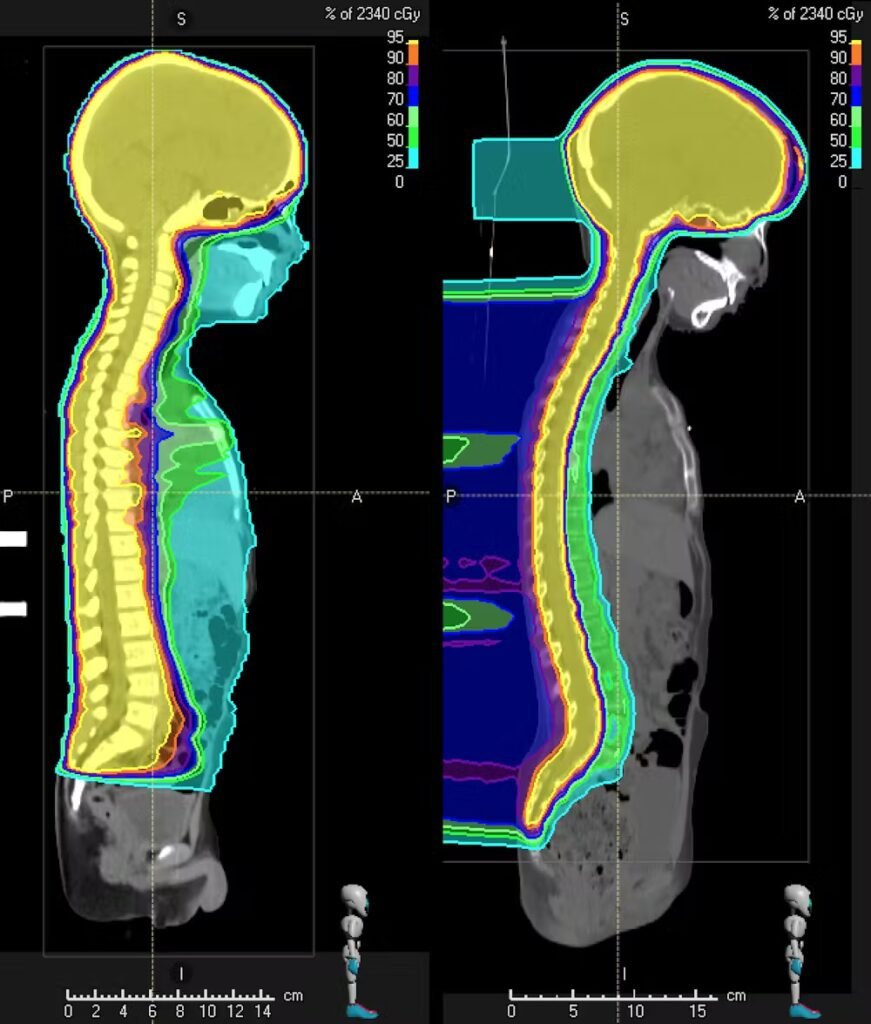

• Παιδιατρικοί ασθενείς, επειδή η ελαχιστοποίηση της δόσης στους υγιείς ιστούς μειώνει τον κίνδυνο όψιμων επιπλοκών και δευτερογενών νεοπλασιών.Όγκοι κοντά σε κρίσιμα όργανα (π.χ. εγκέφαλος, οφθαλμοί, νωτιαίος μυελός, στέλεχος εγκεφάλου), όπου ακόμη και μικρή μείωση της δόσης σε ευαίσθητες δομές μπορεί να είναι καθοριστική (Photo 1).

Παιδιατρικοί Ασθενείς

Photo 1